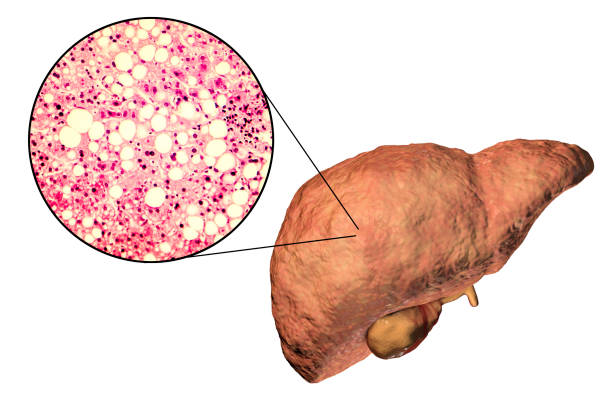

간경화 초기증상은 증상이 나타나지 않거나, 미미한 증상만 나타나기 때문에, 무시하고 지나치기 쉬운 경우가 많습니다. 하지만, 이러한 초기 증상을 간과하면 질병이 진행되어 치료가 어려워질 수 있습니다. 따라서, 간경화 초기증상을 발견하면 적절한 검사와 치료를 받아 조기에 질병을 예방하고 치료할 수 있습니다. 따라서 이번 시간에는 간경화 초기증상에 대해 자세히 알아보도록 하겠습니다.